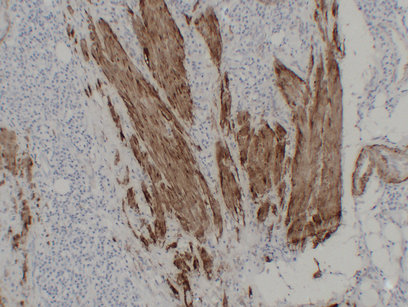

ARG66482 anti-Calponin 1 antibody IHC-P image

Immunohistochemistry: Paraffin-embedded Human leiomyoma stained with ARG66482 anti-Calponin 1 antibody at 1:200 (4°C, overnight). Antigen Retrieval: Citric acid buffer (pH 6.0) was used.